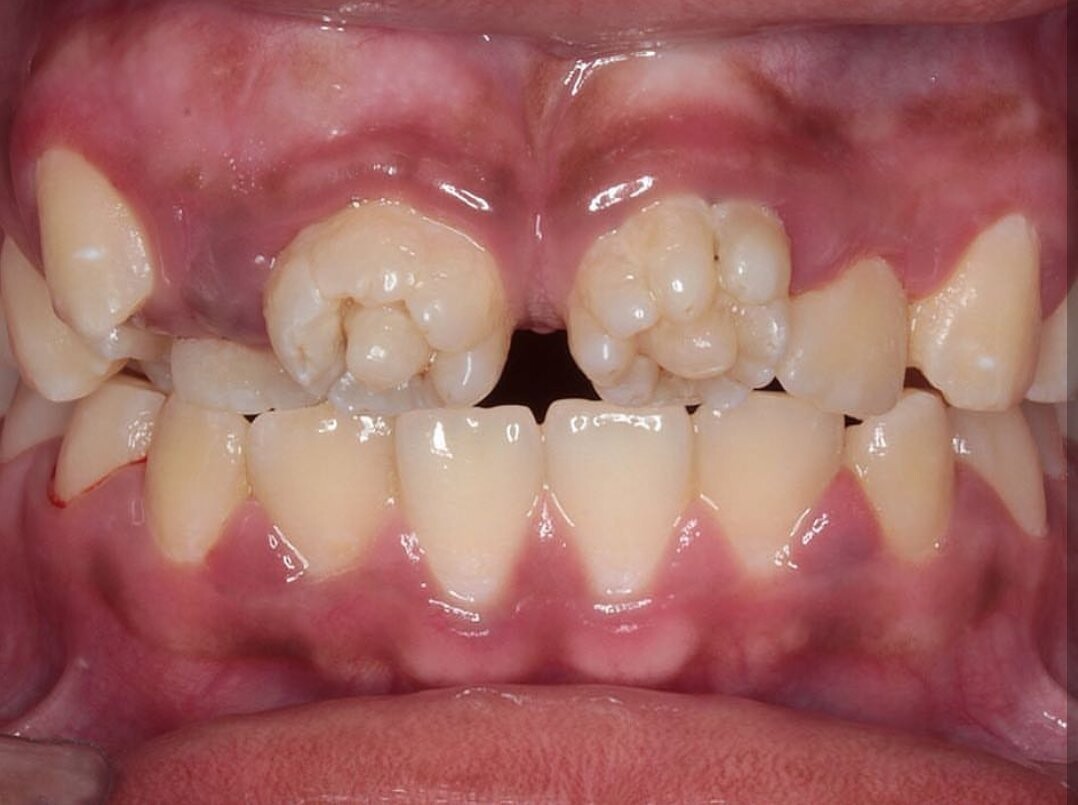

Mulberries. They sound like something you find in a scrumptious pie or jam. Mulberry molars, on the other hand, are a tough pill to swallow. After your child loses their baby teeth, their permanent teeth come in when they're around 5 or 6. Occasionally these fresh molars are abnormally shaped with small bumps, reminiscent of mulberry fruits, according to the Rutgers School of Dental Medicine. While mulberry molars can be alarming for parents — they can be easily treated.

Often, dentists in developed countries have never treated a case of mulberry molars, notes the Head and Neck Pathology report. But they should be able to identify it as the bumpy surface makes the condition very recognizable. Syphilis is diagnosed via a blood test. Antibodies to the bacteria are present in the blood of those with syphilis. It's a severe condition if passed along to babies — consequently, pregnant women should be tested.

Cavities commonly occur if mulberry molars are present. For that reason, crown restorations help not only the look of the teeth but also their strength. Your pediatrician should be able to treat syphilis in children with mulberry teeth by administering penicillin. If allergic to penicillin, antibiotics may also be a course of action.